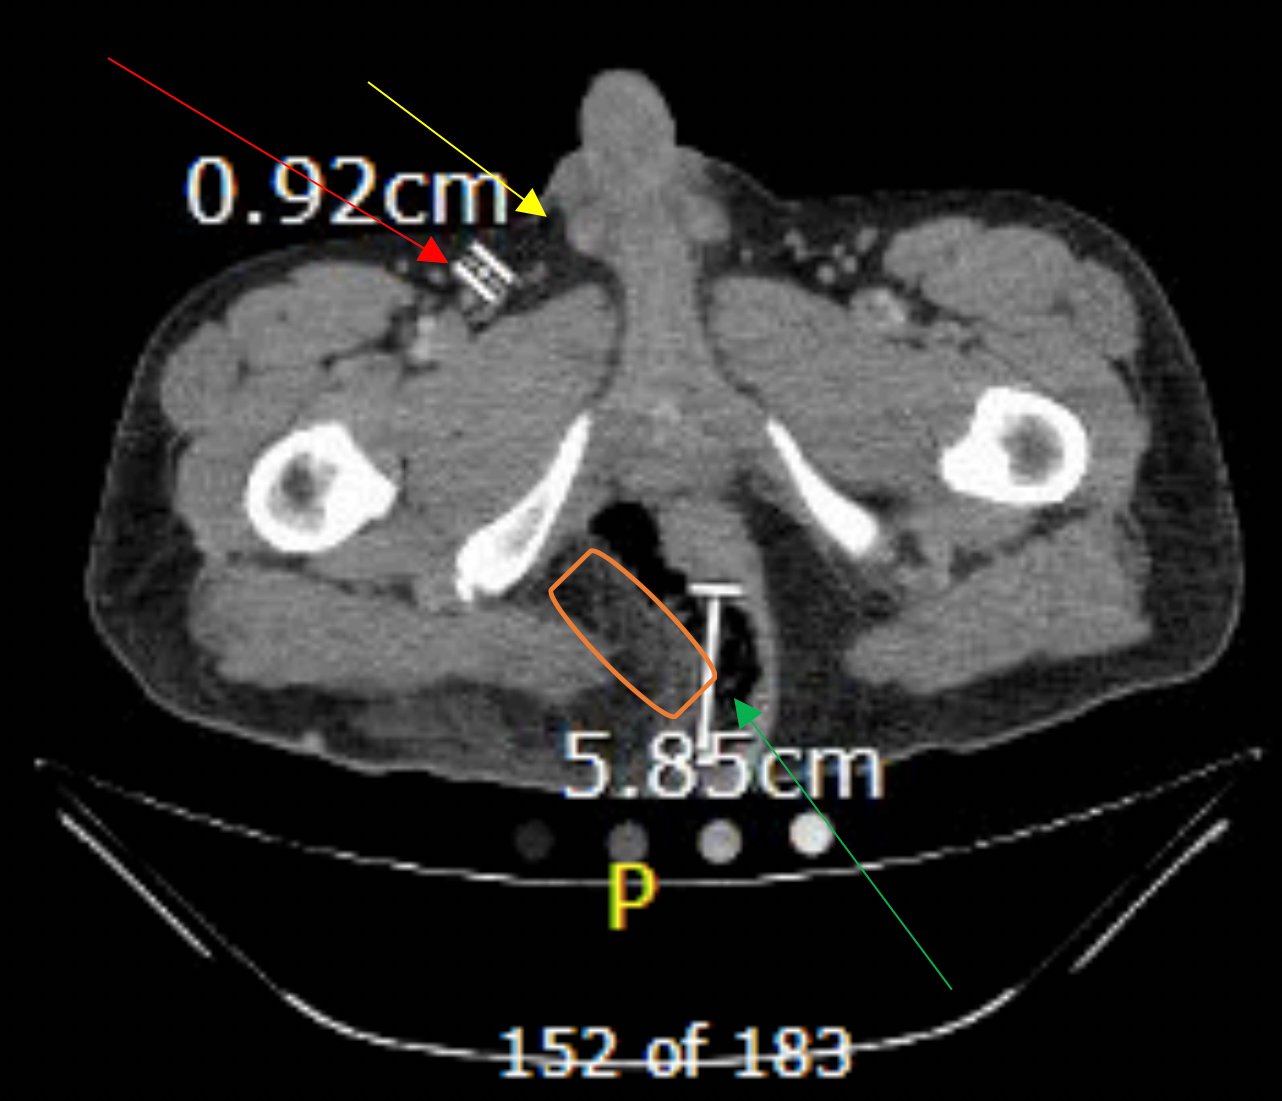

The computed tomography (CT) of the abdomen and pelvis revealed significant subcutaneous gas tracking along the perineum and right gluteal region (orange outline) into the scrotum with associated scrotal edema (yellow arrow) and subcutaneous inflammatory fat stranding of 0.92 cm (red arrow) consistent with Fournier’s gangrene. There is early fluid loculation along the right medial gluteal cleft of 5.85 cm (green arrow) without a sizeable drainable abscess seen.